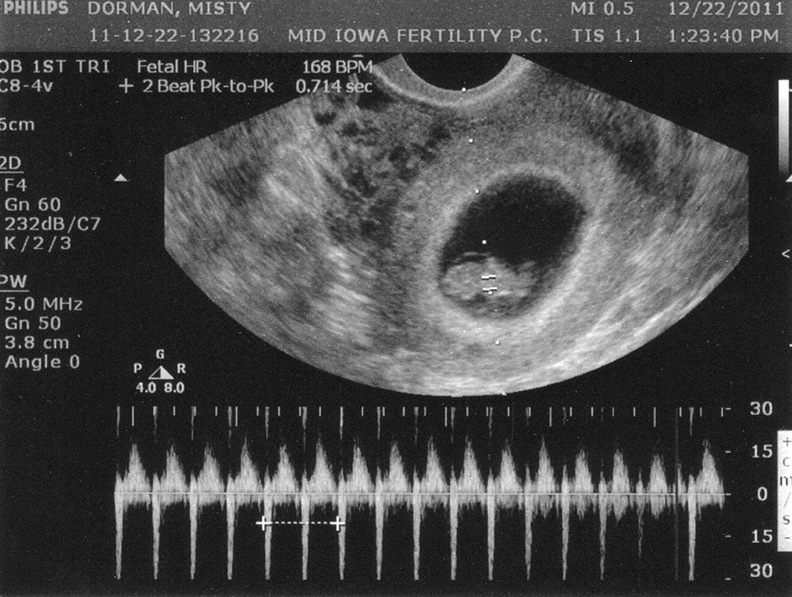

Phụ nữ mang thai sẽ bắt đầu đi siêu âm thai lần đầu tiên vào tuần thai thứ 7. Việc siêu âm thai sẽ xác định sự phát triển của thai và phôi có ổn định hay không. Trong đó, siêu âm đo nhịp tim thai vào tuần 7 là điều rất quan trọng vì có thể hỗ trợ bác sĩ đưa ra các phương pháp chăm sóc thai kỳ cho mẹ.

Thai kỳ tuần thứ 7 - 10 là thời điểm siêu âm thai rất quan trọng mà các mẹ bầu không được bỏ qua. Vì lúc này thai nhi đã hình thành nên qua siêu âm sẽ tính được tuổi thai nhi chính xác nhất. Phôi thai là yếu tố giúp xác định đặc điểm của sự phát triển thai nhi tại giai đoạn này nên rất quan trọng.

Để siêu âm thai nhi ở giai đoạn này, có hai cách gồm soi qua bụng hoặc thông qua ngã âm đạo. Khi siêu âm thai 7 tuần tuổi qua âm đạo, sẽ cung cấp hình ảnh trực quan tốt và chính xác nhất do máy không phải xử lý qua nhiều lớp cơ và lớp mô để đưa ra hình ảnh.

Khi siêu âm đầu dò hay còn gọi là siêu âm qua ngã âm đạo, đầu dò được đặt trong âm đạo của mẹ bầu, truyền các sóng âm thanh qua cổ tử cung và trực tiếp vào tử cung. Với cách này, không cần thiết phải làm căng bàng quang. Trong khi siêu âm qua bụng thì cần phải làm căng bàng quang, nâng tử cung cao hơn để có thể nhìn thấy rõ hơn phôi trong khung xương chậu. Khi thai nhi lớn hơn, tử cung mở rộng không còn được chứa trong vành chậu nên không cần làm căng bàng quang.

Tim thai được hình thành rất sớm, thường xuất hiện vào khoảng tuần thứ 6 hay ngày thứ 16 của thai kỳ. Đến tuần thứ 7 của thai kỳ, nhịp tim thai nhi lớn dần lên và bắt đầu phân chia thành hai buồng trái và phải, đã xuất hiện hai mạch máu ở phôi thai, hình thành hai ống dẫn vào tim thai. Mẹ có thể nhìn thấy và đo được những điểm sáng nhấp nháy trên màn hình của máy siêu âm.

Nếu phát hiện tim thai, mẹ bầu thường thắc mắc tim thai tuần 7 bao nhiêu là bình thường. Nhịp đập bình thường của tim thai bắt đầu từ 90 - 110 nhịp/phút và tăng mỗi ngày. Nhịp tim thai vẫn tăng cho đến khi đạt đỉnh điểm vào khoảng tuần thai thứ 9 với nhịp đập từ 140 - 170 nhịp/phút cho bé trai lẫn bé gái. Nếu em bé cựa quậy nhiều, nhịp tim có thể tăng nhanh đến 180 lần/phút.